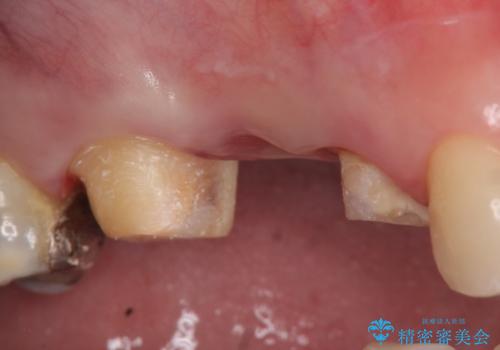

- 右上の奥歯でものを咬むと痛むので診て欲しいといらっしゃった方の症例です。

診査の結果、歯根が破折しており保存不可能だったため抜歯し、ブリッジによる補綴を行いました。